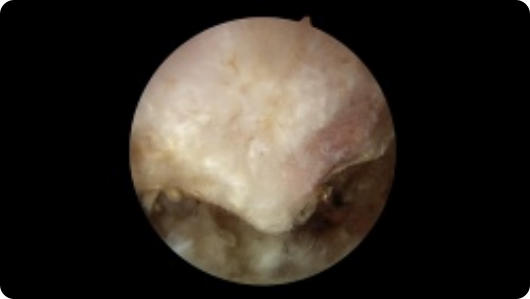

Arthroscopic image of a bone spur Arthroscopic image of a removed bone spur

Bone Spur

Bone Spur Removed